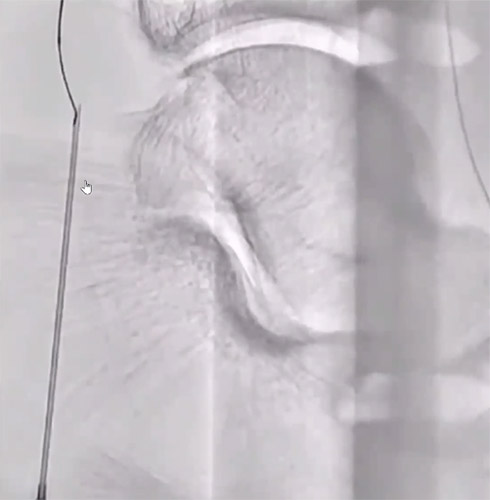

BKについてはATAは開存しており、PTAが途中から閉塞していることを確認した。【図3】

まずはエコーガイド下にPTAの穿刺を試みるが非常にシビアな石灰化に阻まれ穿刺不可となった。PTAの穿刺は諦め、開存しているATAを穿刺しZizai130cmガイド下に0.014inch 1gガイドワイヤーを使用しワイヤリングを実施。ATA入口部付近でZizaiから先端造影を実施。PTAが途中から閉塞していることを確認。【図4】ATAからPTAへワイヤーを反転させて、ワイヤーに追従させる形でZizaiを持ち込んだところ、先端部の柔軟性が高いことからワイヤーへスムーズにZizaiが追従出来たと考える。